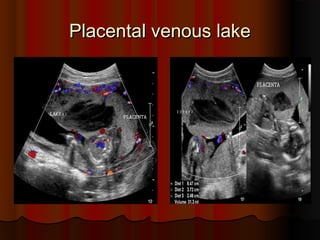

Placental venous lake

This placenta, in a 28 week pregnancy shows a

large hypoechoic

large hypoechoic (

(almost anechoic

almost anechoic)

), measuring

, measuring

5 x 3.5 cms

5 x 3.5 cms.

. in size

in size.

. Some particulate matter

Some particulate matter

was seen flowing through this area, which was

closer to the fetal surface of the placenta

closer to the fetal surface of the placenta.

. These

These

ultrasound images suggest a typical appearance

of a large venous lake in the placenta

of a large venous lake in the placenta.

. Color

Color

Doppler image showed no major flow pattern

within this placental lake

within this placental lake.

. The fine, echogenic

The fine, echogenic

strands within the lesion appear to be nothing

more than artefacts produced by slow flowing

blood within the lesion

blood within the lesion.

.

Placental venous lake Placentalvenous lake This placenta, in a 28 week pregnancy shows a This placenta, in a 28 week pregnancy shows a large hypoechoic large hypoechoic ( (almost anechoic almost anechoic) ), measuring , measuring 5 x 3.5 cms 5 x 3.5 cms. . in size in size. . Some particulate matter Some particulate matter was seen flowing through this area, which was was seen flowing through this area, which was closer to the fetal surface of the placenta closer to the fetal surface of the placenta. . These These ultrasound images suggest a typical appearance ultrasound images suggest a typical appearance of a large venous lake in the placenta of a large venous lake in the placenta. . Color Color Doppler image showed no major flow pattern Doppler image showed no major flow pattern within this placental lake within this placental lake. . The fine, echogenic The fine, echogenic strands within the lesion appear to be nothing strands within the lesion appear to be nothing more than artefacts produced by slow flowing more than artefacts produced by slow flowing blood within the lesion blood within the lesion. .